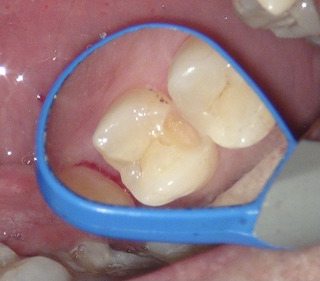

虫歯を全部とったところ レジンを詰め終わったところ